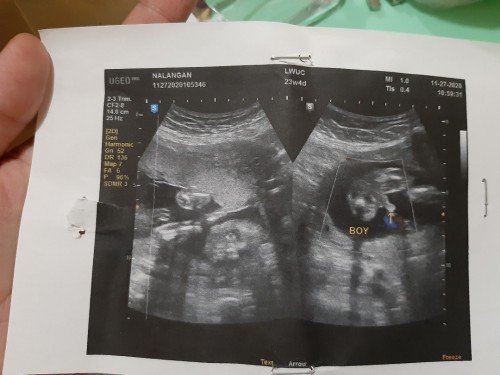

Ultrasound

Hello mga momsh. May nabasa po ako dito na nagkamali ung ultrasound nila for gender. Eto po kaya sakin sure na? Thank u mga momsh. #pregnancy #theasianparentph

sa tingin nyo po mga mommies sigurado na baby boy na po ba baby ko ☺️☺️ kasi puro blue na binili kong gamit nya hehehe

it's a boy tlga mamshie , kc sbi if girl same like hamburger ung nkikita po s ultrasound..

Hehe kitang kita momsh ang lawit. Same sa scan ko

Momsh clear na boy na talaga. Kita agad 😊.

sure na po yan kitang kita ung lawit.😊

klarong klaro ang lawit hehehehe